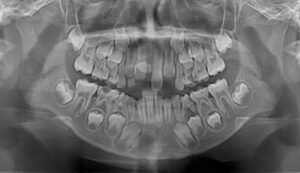

Brezilya’da 11 yaşındaki bir kız çocuğunda tespit edilen sıra dışı diş sayısı, tıp dünyasında dikkat çekti. Yapılan incelemelerde çocuğun ağzında...